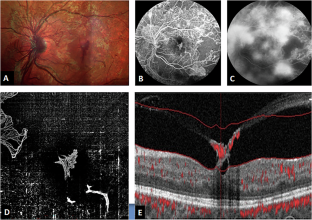

Eyes with proliferative diabetic retinopathy (PDR) and DFN underwent OCTA imaging; defined as surface retinal neovascularization within the central foveal 1 mm diameter circle. 3 × 3 and 6 × 6 mm2 choriocapillaris and superficial and deep retinal capillary plexus (SCP and DCP) slabs were extracted to evaluate adjusted flow index (AFI) as a surrogate for blood flow. For choriocapillaris flow; total, subfoveal and extrafoveal AFI were assessed, while only total AFI was calculated for SCP and DCP. These findings were compared to healthy controls and eyes with PDR with no DFN.

18 eyes of 18 patients were included in each of the 3 groups: healthy controls, PDR with and without DFN. Choriocapillaris AFI was significantly lower in PDR with DFN than healthy controls in all but the 6 × 6 mm2 extrafoveal AFI (p < 0.01). PDR with DFN also showed a lower AFI compared to eyes without DFN, but only in the 3 × 3 mm2 total and subfoveal AFI (p = 0.01). SCP and DCP AFI were not statistically significant.

Our findings suggest that choroidal hypoperfusion may be a potential driving factor for the development of DFN. The detection of these changes in the smaller scans of the total and subfoveal areas suggests a rather exaggerated and localized subfoveal distribution of ischaemia. Larger longitudinal studies are needed to explore the use of subfoveal choroidal AFI as a prognostic sign for DFN.